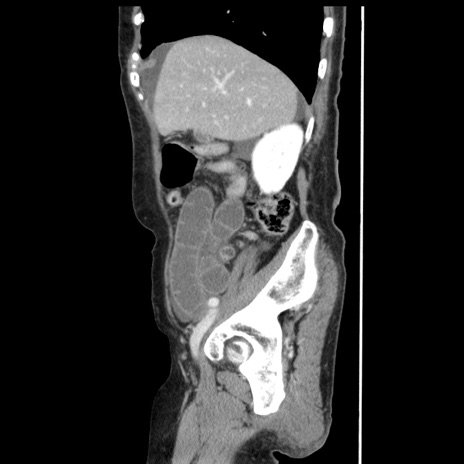

症例1(矢状断像)

【症例】80歳代女性

【主訴】腹痛

【現病歴】8時間前から腹痛あり来院。

【既往歴】糖尿病、脂質異常症、子宮体癌にて子宮全摘術

【身体所見】意識清明・会話良好だが腹痛で苦悶様、全腹部にわたって反跳痛と圧痛あり

【データ】WBC 13600、CRP 0.14、LDH 224、CK 90